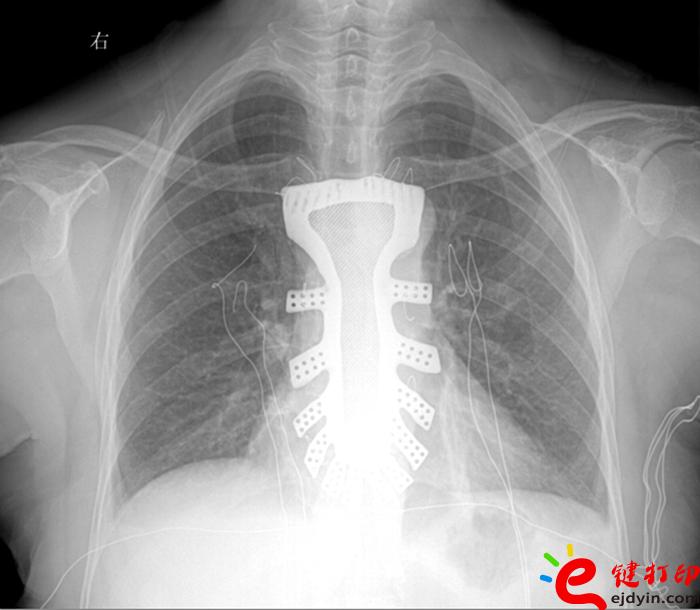

當然,“3D打印”的世界遠不止如此。據(jù)參加大會的專家和企業(yè)負責人介紹,目前“3D打印”已被運用在文化創(chuàng)意、文物修復、生物醫(yī)療、工業(yè)設計等多個領域。如,在航空航天器材上,一些關鍵零部件采用“3D打印”一次成型,使得其功能更加實用,重量大幅減少;在醫(yī)療領域,“3D打印”被運用于牙齒再造和骨骼修復等方面,從而使治療更加精準。